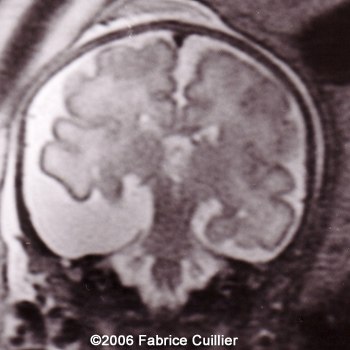

The following images are obtained in a 3rd trimester fetus:

The final diagnosis was: Arachnoid cyst